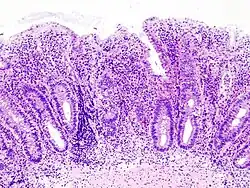

H&E stain of a colonic biopsy showing a crypt abscess, a classic finding in ulcerative colitis

Biopsy sample (H&E stain) that demonstrates marked lymphocytic infiltration (blue/purple) of the intestinal mucosa and architectural distortion of the crypts.

Crypt abscess. H&E stain.

Biopsies of the mucosa are taken during endoscopy to confirm the diagnosis of UC and differentiate it from Crohn's disease, which is managed differently clinically. Histologic findings in ulcerative colitis include: distortion of crypt architecture, crypt abscesses, and inflammatory cells in the mucosa (lymphocytes, plasma cells, and granulocytes).[28] Unlike the transmural inflammation seen in Crohn's disease, the inflammation of ulcerative colitis is limited to the mucosa.[28]